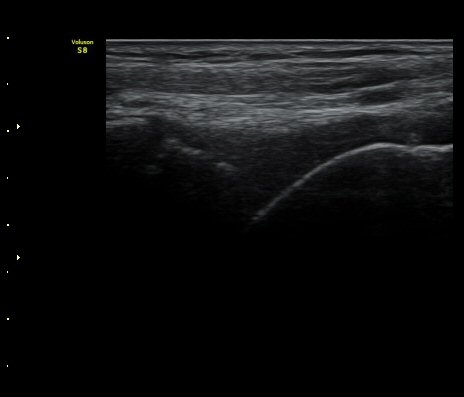

¹ß¸ñ°üÀý Á¾´Ü¸é°Ë»ç¿¡¼­ °üÀý³» ¼ö¾×Àú·ù°¡ °üÂûµÈ´Ù(±×¸² 1).

Àü°Å°ñºñ°ñÀδë Á¾´Ü¸é°Ë»ç»ó Àδë ÀδëÀÇ Àú¿¡ÄÚ ºÎÁ¾°ú ºñ°ñ

ºÎÂøºÎ ¹Ì¼¼ °ß¿­°ñÀýÀÌ °üÂûµÈ´Ù(±×¸² 3, 4).

ÃÊÀ½ÆÄÅõ½ÃÇÏ ºÎÇϰ˻翡¼­ ºñ°ñ°ú °ß¿­°ñÀý °ñÆí»çÀÌ¿Í ºñ°ñ°ú °Å°ñ »çÀ̰¡ ¹ú¾îÁø´Ù

(樨毢 1)